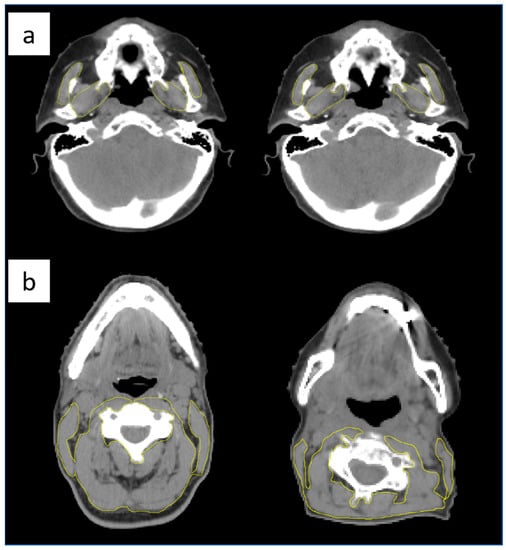

- Masticatory muscles (MM): identified as the masseter and the pterygoid muscles, taken on the first CT slice showing the bilateral mandibular notches when scrolling from caudal to cranial direction (Figure 2a) [40]. The CSA of MM (CSA-MM) was used to estimate the L3-SMI, based on the model proposed by Chang et al. [40] and sarcopenia was then defined using the sex-specific cut off points for L3- SMI of <38.5 cm2/m2 for women and <52.4 cm2/m2 for men, as described by Prado et al. [46].

- Paravertebral and sternocleidomastoid muscles: taken at the level of the third cervical vertebra (C3), at the first CT slice identifying the entire vertebral arch of C3 when scrolling from caudal to cranial direction (Figure 2b). The CSA of these muscles at the level of C3 (CSA-C3) was then used to estimate the L3-SMI based on the formula validated by Swartz et al. [35]. Sarcopenia was then defined using the proposed sex-specific cut-off points for L3- SMI of <30.6 cm2/m2 for women and <42.4 cm2/m2 for man by Van Rijn-Dekker et al. [30].